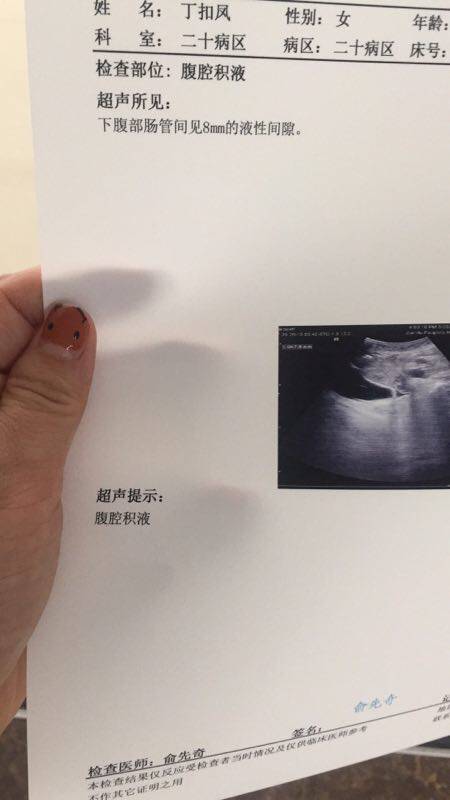

求助腹腔积液

今天做检查妈妈有腹腔积液了。求助大家有没有类似的病例?是做引流吗还是…?求助,谢谢

医生怎么说,B超检查一下看,多肯定是要引流,要不人会很不舒服的。

医生说一点点很少,不舒服很有可能是有气

如果不是很多就不需要引流,自行吸收即可!